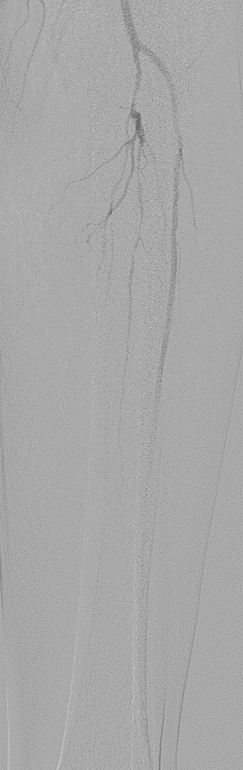

★ Case 1

noproximal stump in SFA,>250mm

★ Case 2

significantdistal collaterals